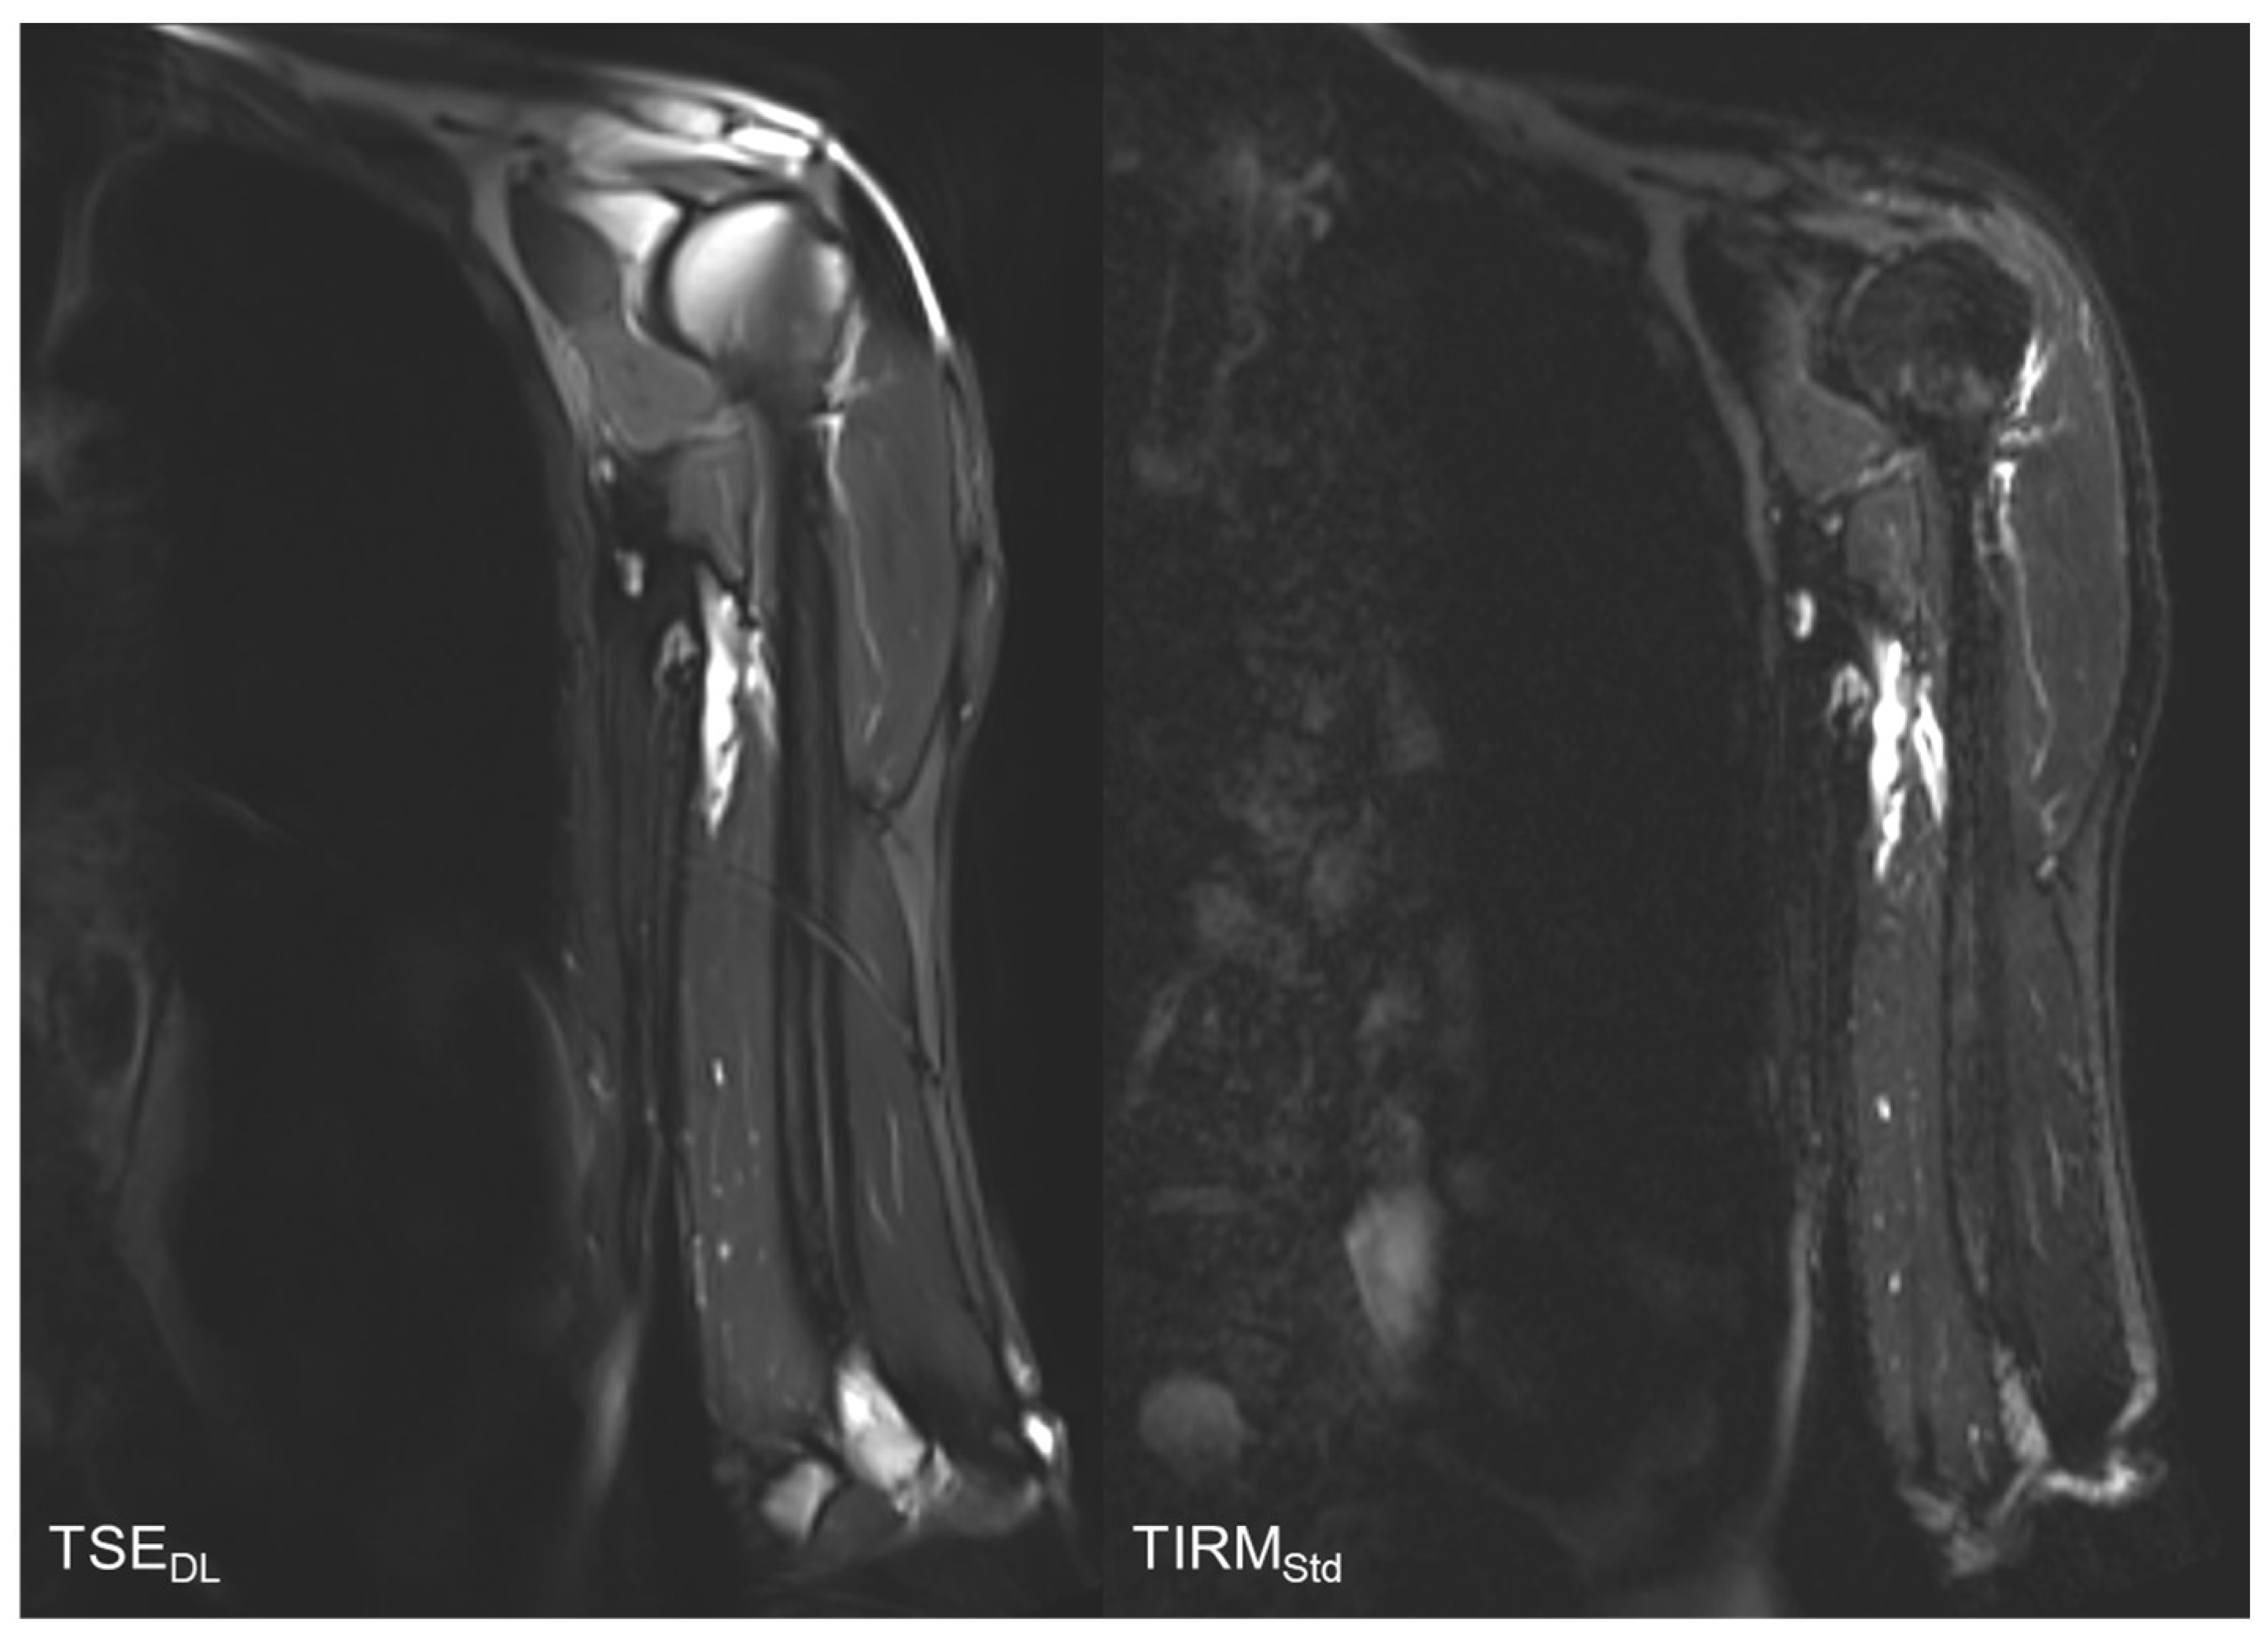

Reduction in Acquisition Time and Improvement in Image Quality in T2-Weighted MR Imaging of Musculoskeletal Tumors of the Extremities Using a Novel Deep Learning-Based Reconstruction Technique in a Turbo Spin Echo (TSE) Sequence

3.4. Qualitative Image Analysis